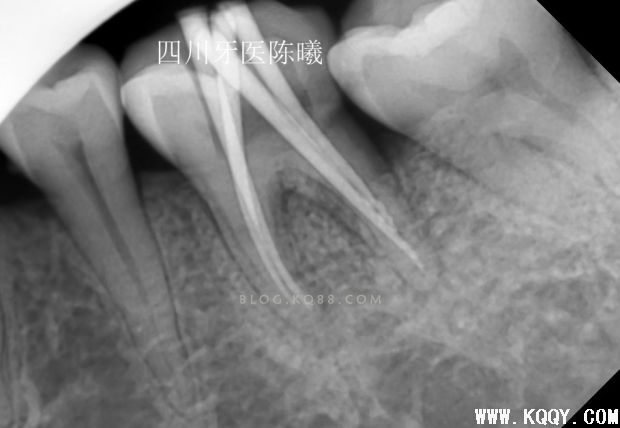

试尖完发现近中稍欠,远中颊根部到位,于是用20#25#K挫稍微挫了下根尖3分之1,远颊根挫时病人告知有疼痛,依然没有重视,在冲洗的时候发现少许没有去除干净的氢氧化钙糊剂从根管内溢出,又是一个问题,这下觉得应该到位了,那就充填吧,于是用试尖的牙胶尖号数充填,结果如下

从这3张片子上可以看出近远中都有超填,唉,重来吧!(发博客都一波三折,这都第四次编辑了,不容易啊)跟病人说清楚情况取得同意后,准备重新充填,但是这个时候不知道近远中超填的是颊根还是舌根,又一个问题,只有想办法,我去掉近远中颊根充填物后照片(远中充填得很密合,废好大功夫才取出来)

可以看出在取出近远中颊根充填物后,远中依然超填,说明远中超填的是舌根,然后觉得近中舌根充填锥度也不连续,干脆全部取出重新做!